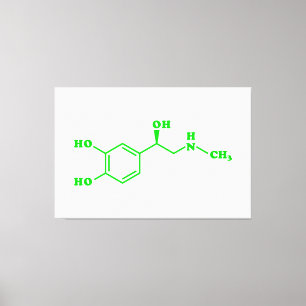

Lienzo Fórmula Química Molecular Adrenalina

Precio 572,80 €